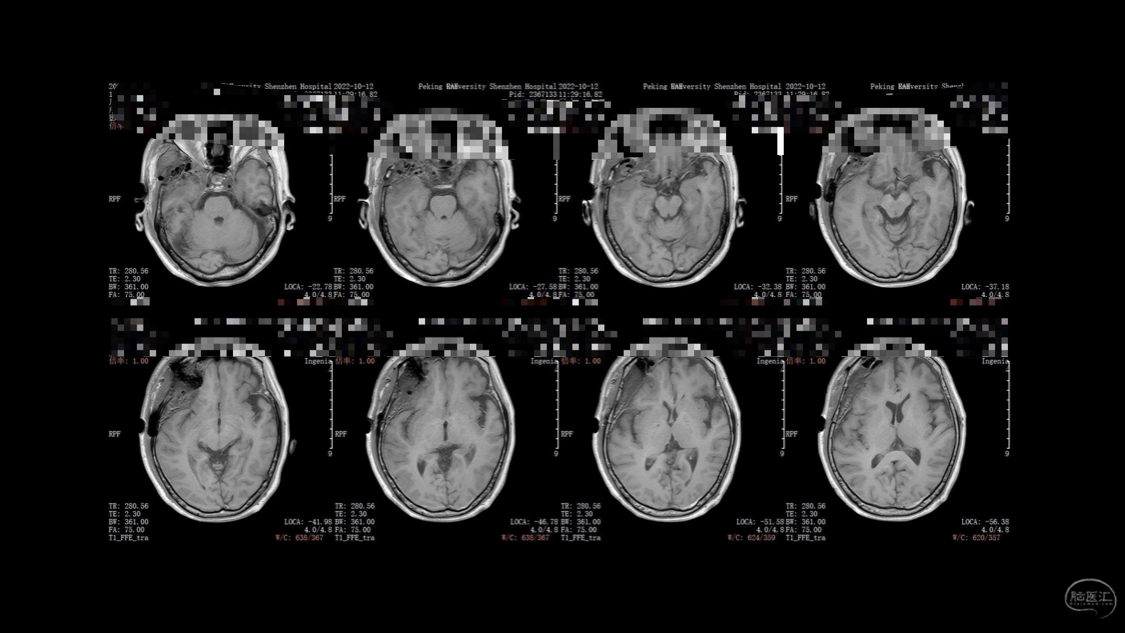

陈保东教授手术作品-右眶内及海绵窦旁孤立性纤维瘤